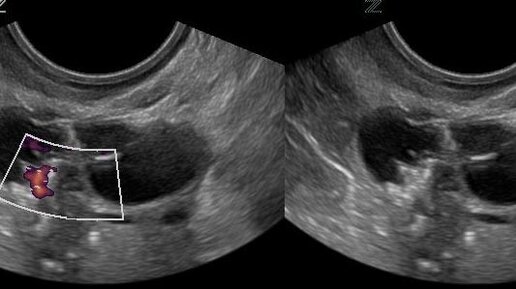

Кистой яичника называют образование, которое представляет собой полость, заполненную жидкостью и окруженную плотной капсулой. Опухоль имеет доброкачественный характер. Рост обусловлен увеличением объема жидкости. На своём Телеграм-канале мы публикуем клинические случаи и посты от наших акушеров-гинекологов и репродуктологов. Подпишитесь, чтобы узнавать больше полезного о мужском и женском здоровье. Виды кисты Кисты яичника отличаются: По каким признакам можно определить кисту яичника Очень часто формирование кисты не сопровождается какими-либо симптомами...

Киста яичника — это заполненное жидкостью полостное образование на поверхности или внутри яичника. Такие кисты встречаются у женщин любого возраста, но чаще всего диагностируются в репродуктивном возрасте. Какие типы кист существуют? Какие их сопровождают симптомы? Как их диагностируют и лечат? Каждый тип кисты яичника имеет свои особенности, которые определяют подход к лечению. Наиболее распространенный тип кист. Такие кисты бывают: Образуются в результате эндометриоза, при котором подобная эндометрию ткань растет за пределами матки, в том числе на яичниках...